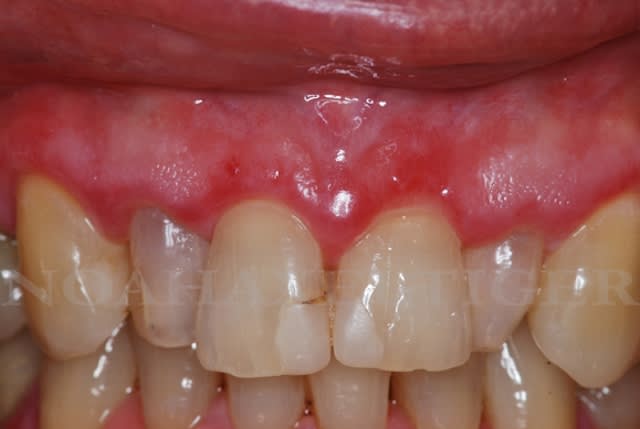

Besoin d'aide pour un cas de lichen plan, pemphigoïde

cela semble tout à fait compatible avec une LPB avec localisations bipolaires ça peut être un SVVG = syndrome vulvo-vagino-gingival.

Je ne pencherais pas pour une pemphigoide bulleuse mais plus pour une pemphigoide cicatriciel à choisir entre les 2.

mais je reste sur l'idée d'un lichen avec localisation sur les muqueuses buccale et genitale

la pemphigoide bulleuse a des signes cutanée plus marqués

prurit très marqué (pouvant longuement précéder l'apparition des lésions) avec des plaques urticariennes plus ou moins symétriques sur le corps, localisées sur les faces de flexion des membres, sur les parties internes des cuisses puis sur les bras et le tronc.

Des bulles tendues apparaissent secondairement; prurigineuses, à contenu clair, parfois hémorragique et trouble, souvent de grande taille (de 0,5 à plusieurs cm), elles se localisent en bordure des plaques urticariennes (papules et plaques érythémateuses et prurigineuses) ou parfois en peau saine. Ces bulles finissent par se rompre créant des érosions souvent couvertes de croûtes guérissant sans laisser de cicatrices

L'atteinte buccale est rare (10 à 20% des cas) et apparaît souvent dans un second temps. Elle consiste en bulles sur bases énanthémateuses, beaucoup moins fragiles que celles du pemphigus car le décollement est plus profond. Ces bulles perdent leur toit en laissant des ulcérations rouges plus ou moins recouvertes du reliquat blanchâtre du toit. Ces lésions buccales peuvent être associées à une gingivite desquamative correspondant à une desquamation de la gencive adhérente sur un fond érythémateux intense

la pemphigoide cicatricielle=Pemphigoïde bénigne des muqueuses=Dermatite bulleuse mucosynéchiante et atrophiante de Lortat-jacob

La pemphigoïde cicatricielle est une dermatose bulleuse rare, proche de la pemphigoïde bulleuse mais qui en diffère par sa clinique car elle affecte généralement les muqueuses.

En effet l'atteinte cutanée n'est observée que dans 25 % des cas, et jamais de façon très importante, avec des lésions ressemblant à celles de la pemphigoïde bulleuse (bulles tendues, à contenu clair parfois hémorragique et pouvant devenir trouble, souvent de grandes tailles -de 0,5 à plusieurs cm-, elles se situent en bordure de plaques urticariennes (papules et plaques érythémateuses et prurigineuses) ou en peau saine laissant des érosions). La guérison engendre des cicatrices et des grains de millium contrairement à la pemphigoïde bulleuse qui, elle ne laisse pas de cicatrices. Ces lésions cutanées prédominent à la tête et au cou mais peuvent se situer sur d'autres zones du corps.

L'atteinte buccale est commune dans 80 à 90% des cas; elle se présente généralement comme une gingivite desquamative (desquamation de la gencive adhérente sur un fond érythémateux intense) avec rarement des bulles intrabuccales à contenu claire ou hémorragique (siégeant sur le palais, la langue ou la gencive) laissant des ulcérations chroniques douloureuses. La guérison entraine des cicatrices susceptibles de constituer des synéchies entre la langue, la muqueuse jugale et le voile du palais. Le sillon gingivo-jugale peut se combler et l'orifice buccal se rétrécir.

mais ca peut etre juste un lichen plan localisé sur la muqueuse buccale et genital (plus ds mon idée)

avec surveillance pour pas dériver vers un carcinome épidermoïde (0,4 à 2,5%).

POur répondre à Noah,

S'il s'agit d'une PC (pemphigoïde cicatricielle) cela impose un bilan général avec notamment consultation ORL et ophtalmo obligatoire.

Pour faire ou éliminer le diagnostic il faut passer par les tests d'immnufluorescence direct et indirect. IFI et IFD. L'histologie simple est peu contributive.

Tu peux très bien faire le prélèvement toi même sur une portion de muqueuse ou gencive saine. Mais faut se mettre en rapport avec le labo d'analyse voire carrément avec un labo d'histopathodermato qui existe dans les services de dermato des CHU. Attention, le milieu de transport est spécifique, pas de formol. Je dis ça car tout le monde est pas au courant.

Concernant un LPB le bilan général impose en un minimum d'une prise de sang classsique avec les enzymes hépatiques, et une glycémie. En principe faut aussi faire une sérologie VHC car association décrite dans la littérature je ne sais plus à quel pourcentage.

Fait faire aussi en partenariat avec le médecin de famille à tout hasard une radio des poumons juste pour pas laisser de côté d'une autre hypothèse. Voire écho hépatique et pancréatique.

En effet, le LPB la PC mais le plus souvent le pemphigus vulgaire peuvent n'être que des épiphénomènes. Je m'explique. Ils peuvent être des manifestations paranéoplasiques. Un cancer du poumon se voit généralement à la radio et ça mange pas de pain.

Si le bilan est négatif, bon faut rester sur une hypothèse psycho-somatique. C'est très fréquent sur les pathologies dermatologiques.